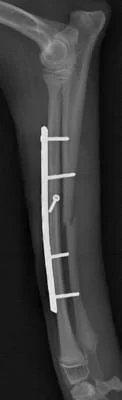

左前肢

橈骨・尺骨ともに癒合してますし、

橈骨の髄腔もきちんと確認できます。

極端な骨硬化像も認めないので経過観察終了としました。